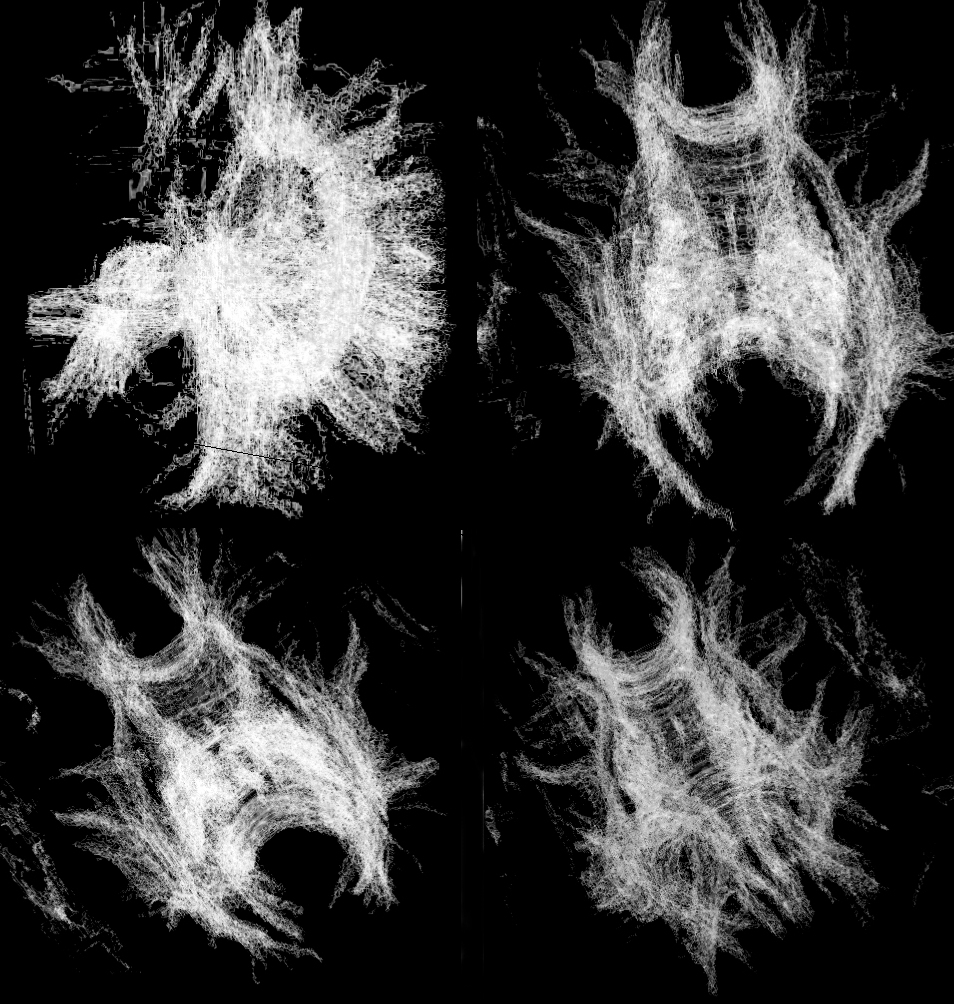

Visualization of the nerve fiber tracts in the brain using a direct volume rendered LIC texture

2004-11-06, Sayuj Harindranath, Desmond Chik, Moqing Zhang, Xin Zhang, Jacky Kwok |

Direct Volume Rendering Fast Line Integral Convolution Image of Human Brain Nerve Fiber Tracts

2004-10-22, Bo Li, Jing Li, Sharon Liu, Jessica Qu, Fung Yang |